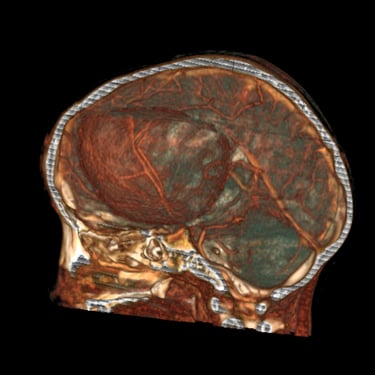

El absceso cerebral es una infección localizada del parénquima cerebral que produce acumulación de pus e inflamación, generando cefalea, fiebre, alteración del estado de conciencia o déficit neurológico focal. El diagnóstico temprano es fundamental para evitar complicaciones graves. La tomografía cerebral con contraste es el estudio de elección inicial, ya que permite visualizar una lesión hipodensa con realce en anillo característico. Posteriormente, la resonancia magnética complementa la evaluación. El tratamiento combina antibioticoterapia dirigida y, en casos seleccionados, drenaje quirúrgico o resección. La detección oportuna mediante imágenes mejora significativamente el pronóstico del paciente.